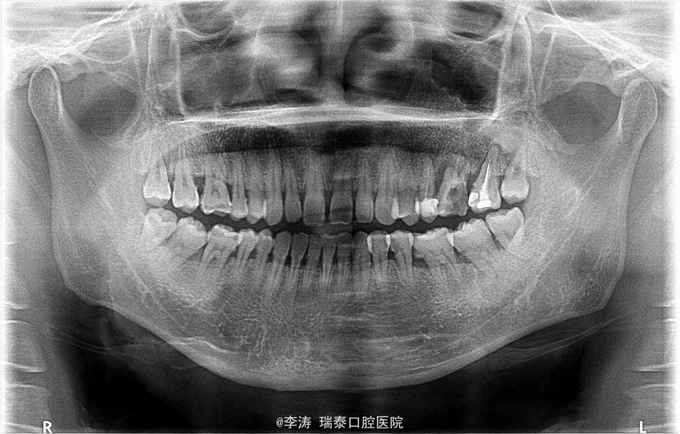

根尖区病变牙的治疗一例

牙骨质瘤 牙骨质瘤

26残冠 25,27根管治疗不到位 27牙根尖区高密度影 所有牙均无临床症状

经多方会诊,确认考虑27牙根尖牙骨质瘤,建议先行根管治疗,然后密切观察 予以拔除26,根管治疗25,27